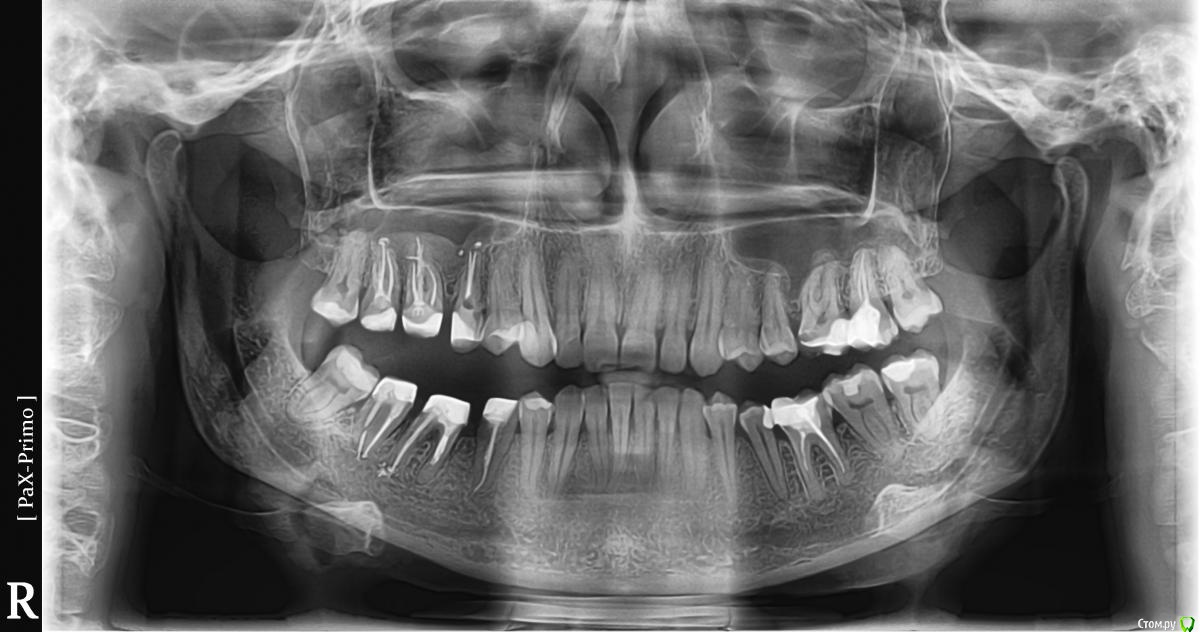

vicTORYa Опубликовано 24 мая, 2016 Поделиться Опубликовано 24 мая, 2016 Здравствуйте.В сентябре 2015 года лечила зубы с правой стороны.Снимок до леченияЛечили нижние 4,5,6,7,8 и верхние 3,4,5,6,7,8 зубы справа. В 5 и 7 верхних зубах случилась перфорация пазухи, врач поставил ультракал на месяц. Остальные зубы запломбировал постоянными пломбами, в каналы гуттаперчю поставил.В октябре пришла долечить 5 и 7 зубы. 5 запломбировали, а в 7 обнаружилась перфорация корня, врач запломбировал этот перфорированный канал какой-то специальной пастой (названия не помню). Два верхних и три нижних подготовил под коронки. Коронки решили ставить позже.Всё ждала, когда боль пройдет, но в некоторых зубах она так и не прошла, на тот момент при нажатии на зубы или постукивание болели 5, 6, 7 верхние (кажется 8 тоже), нижний 7 и немного ныл 5 нижний. Сделала панорамный снимок и пошла к врачу, он направил к ЛОРу так как увидел пятно в пазухе.Снимок на тот моментЛОР послал на КТ пазух.Сказал, что это кистозно-полипозное образование и его нужно удалять.Так ничего и не делала, оставила ситуацию в подвешенном состояние так как я в полной растерянности.На данный момент болят при постукивание верхние 5,6,7, 8 но совсем немного, при нажатие 6,7. Нижний 7 болит при нажатий и постукивание, немного 5 (и как будто ноющая боль бывает).Свежий снимок.Помогите пожалуйста разобраться. Что с этими зубами? Почему они продолжают болеть? Насколько большая проблема материал, выступивший за предел корня? Нет ли вокруг него воспалительного процесса? И что мне с ними делать дальше? Одевать ли коронки? Или может какие-то из них вообще подлежат удалению? Что с пазухой? Если нужны какие-то другие срезы из КТ могу выложить. Заранее спасибо. Ссылка на комментарий